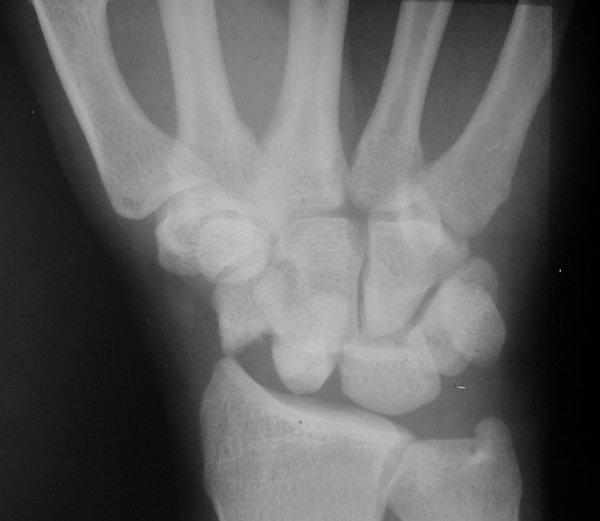

Return to Perilunate Dislocation